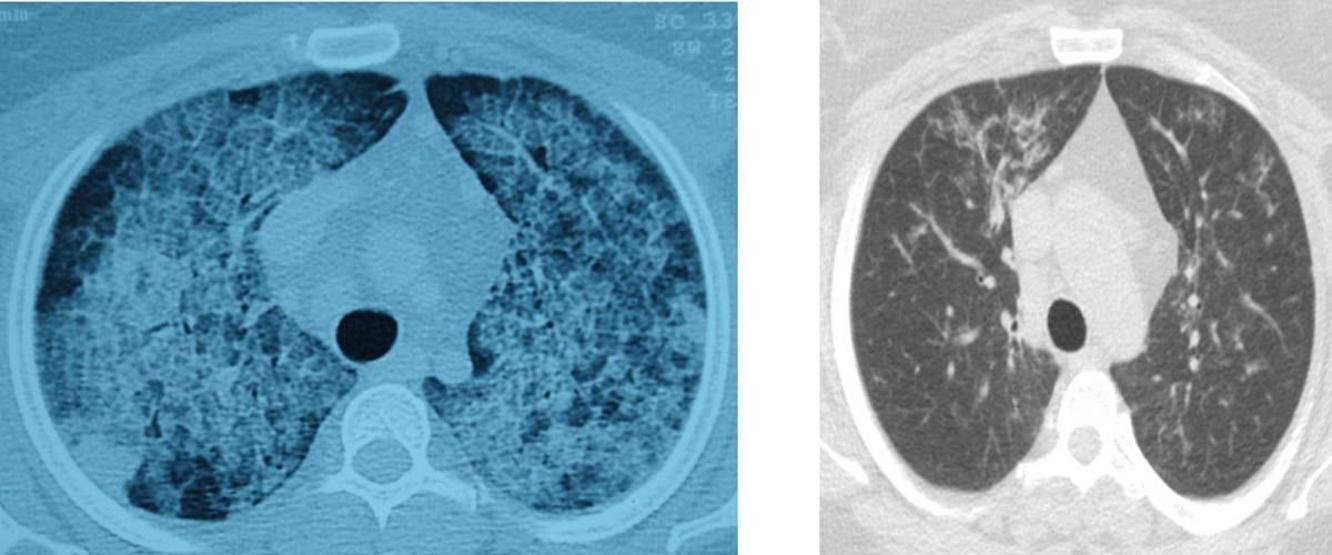

Akciğerde yağ birikmesi sonucu ortaya çıkan nadir hastalıklar akciğer yıkama yöntemiyle tedavi ediliyor. Nefes darlığı şikayeti ile hastaneye başvuran bir kişi bu yöntemle yeniden sağlığına kavuştu. Peki akciğer yıkama yöntemi nedir? Kimlere uygulanır? Detaylar haberde...

Pamukkale Üniversitesi Hastanesi Göğüs Hastalıkları Ana Bilim Dalı Öğretim Üyesi Prof. Dr. Göksel Altınışık Ergur, akciğerlerde yağ birikmesiyle ortaya çıkan nadir hastalıkların akciğer yıkama yöntemiyle başarılı bir şekilde tedavi edildiğini bildirdi.

Ergur, AA muhabirine, hastanede 2007 yılından bu yana 14 hastayı bu yöntemle tedavi ettiklerini söyledi.

Son olarak Isparta'dan nefes darlığı şikayetiyle gelen hastayı tedavi ettiklerini belirten Ergur, "Az rastlanan benzer hastalıklara, dünya genelinde 'öksüz hastalıklar' denmektedir.

Milyonda bir görülen bir hastalık da olsa, ona sahip olan kişi ve ailesi için bu hastalığın çok nadir görülme özelliğinin hiçbir anlam taşımayacağı unutulmamalıdır. Hastalarımızın sağlıkla aldıkları her nefes, bunun için sarf edilen bütün çabalarımıza değer." diye konuştu.

Hastalığın, kişinin kendi yağ ve proteinlerinin temizlenmesiyle görevli hücrelerdeki sorun nedeniyle akciğerlerdeki hava keseciklerinin birikmesi sonucu ortaya çıktığını aktaran Ergur, belirtilerin nefes darlığı, yorgunluk ve aşırı halsizlik olduğunu kaydetti.

Ergur, hastalığın çoğu zaman astımla karıştırıldığını, tanının ancak ileri tetkiklerle konulabildiğini ifade etti.

Sadece deneyimli merkezlerde uygulanabilen akciğer yıkamasının, ameliyathane koşullarında, hastanın uyutularak her seansta 15-20 litre steril su verilmesi ve geri alınması yöntemiyle yapıldığını anlatan Ergur, şunları kaydetti:

"Bazı hastalar kendiliğinden düzelirken bazen yalnızca tek ya da birkaç yıkama yetebilmekte, nadiren sürekli birikim olması nedeniyle akciğer yıkamalarının tekrarlanması gerekebilmektedir.

Bu durumda hastaların yeniden nefeslerine kavuşabilmeleri, deneyimli ekibin bu tedaviyi uygulaması sayesinde olabilmektedir.

Yıkama esnasında başta koyu olan, beklediğinde şişenin dibinde çökelti oluşan yıkama sıvısının rengi giderek açılmakta ve bu durumda yıkama işlemi sonlandırılmaktadır."